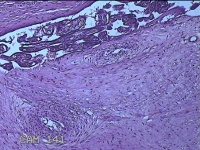

胎盘组织

胎膜早破 早产

停经36+1周,阴道流液3天。

灰白暗红色胎盘组织18x15.5x2.3㎝一个,表面光滑,血管清晰,颜色发暗,绒毛面结节状,轻度糜烂,表面有少许凝血块,切面见绒毛内有部分淤血,边缘蜕膜可见多个小血肿,脐带15x1.5x0.8㎝,切断脐带,见脐血管内有凝血块。